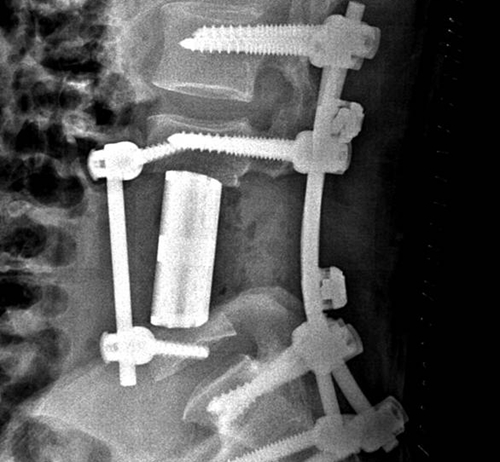

手术中,在钉棒系统的固定下,医生为患者植入了人工椎体。

经过多次多学科会诊讨论,团队最终确定了最佳手术方案:将病变的肿瘤连带被侵犯的椎体整体切除,并用钉棒系统固定后,植入3D打印的个性化人工椎体代替被切除的脊椎。

李浩淼介绍,手术切除了王先生4号腰椎与3号5号各半节椎体,总共长达9厘米,并植入了同样尺寸的人工椎体。术后检查显示,王先生体内的3D打印人工椎体匹配良好,人工两端弧形设计与上下椎体终板贴敷可靠。

而植入体内的人工椎体更体现了3D技术的优越性。金大地介绍,传统的人工椎体仅有固定的几个型号,而通过3D打印技术打印的人工椎体,可以完美匹配患者自身的椎体。此外,3D打印的人工椎体还具有骨头本身的骨质结构,更加方便患者自身的骨质生长并与人工椎体融合,最大限度地避免椎体终板塌陷。